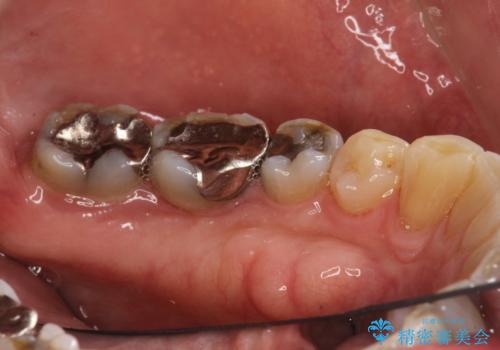

- 歯と歯の間の歯石が気になるとのことで来院されました。PMTC30分コースを行いました。プラークコントロールも悪かったため、歯ブラシ指導も行いました。